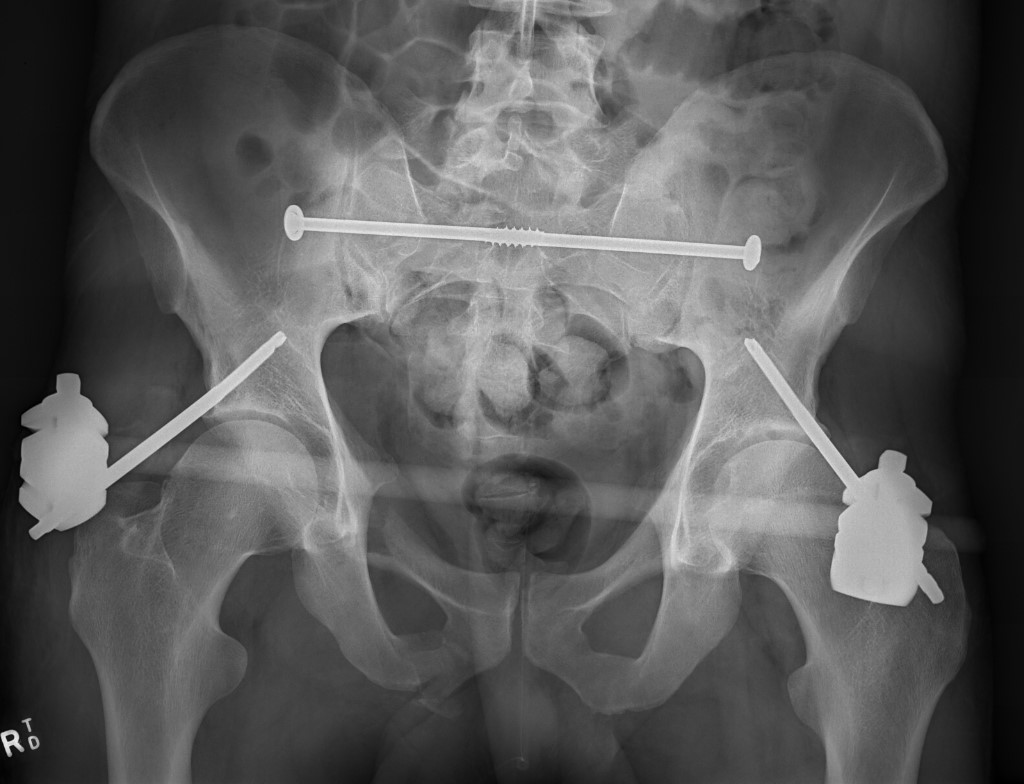

Pelvic ex fixPelvic ex fix 2

External fixation technique